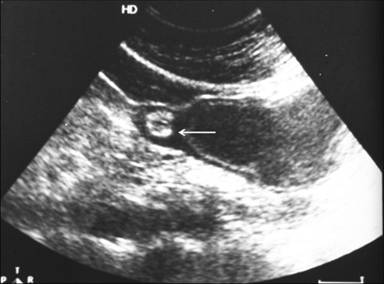

A 30-year-old woman presented with recurrent episodes of dull aching non-radiating abdominal pain of a 6 month duration which was localized in the epigastric region and was non colicky in nature with no relation to meals. It was associated with occasional non-bilious vomiting. There was no history of jaundice, gastrointestinal bleeding, melena, weight loss or altered bowel habits. There was no history of diabetes mellitus, tuberculosis, hypertension or cardiac disease. On examination, she was anicteric, had no pallor and no palpable lumps or tenderness. At admission, her hemoglobin was 11.9 g/dL (reference range: 12.0-14.0 g/dL), total leukocyte count 6,700 mm-3 (reference range: 4,000-9,000 mm-3), serum total bilirubin 0.6 mg/dL (reference range: 0.3-1.3 mg/dL), aspartate transaminase 18 IU/L (reference range: 7-41 IU/L), alanine transaminase 16 IU/L (reference range: 12-38 IU/L), alkaline phosphatase 201 IU/L (reference range: 80-290 IU/L), and serum amylase 112 IU/L (reference range: 22-80 IU/L). A contrast-enhanced CT scan showed a cystic lesion with finger-like projections abutting the pylorus and the antrum of the stomach with an adjacent stippled fat density lesion (Figures 1 and 2). Ultrasound of the abdomen showed an anechoic cystic structure with an inner hyperechoic layer and an outer hypoechoic layer which was contiguous with the muscle layer of the stomach (Figure 3), confirming the diagnosis of a duplication cyst.

Figure 3. A two-layered pattern of the wall of the duplication cyst is visible on ultrasound of the abdomen. The inner layer (mucosa) is hyperechoic and the outer layer (muscular layer) is hypoechoic. The hypoechoic muscular layer of the cyst is continuous with the muscular layer of the antral portion of the stomach (arrow). |

Diagnostic confusion between a pancreatic pseudocyst and cystic degeneration of a gastric tumor may arise. The absence of inflammation of the pancreas or a solid-cystic component and the presence of finger-like projections and sonographic features of a layered pattern should help in a correct diagnosis. CT and MRI may also show a layered pattern as in our case, where the cyst wall had a clear inner hypodense layer and an outer enhancing layer (Figures 2 and 4). Ultrasound can reliably diagnose a duplication cyst when the typical alternating hyperechoic and hypoechoic bowel signal pattern is seen [1]. The presence of ectopic pancreatic rests is less reliably diagnosed on transabdominal ultrasound. Endoscopic ultrasound is a more sensitive modality for detecting and characterizing small submucosal pancreatic rests [3]. However, exophytic serosal pancreatic rests may be detected only by CT and MRI.